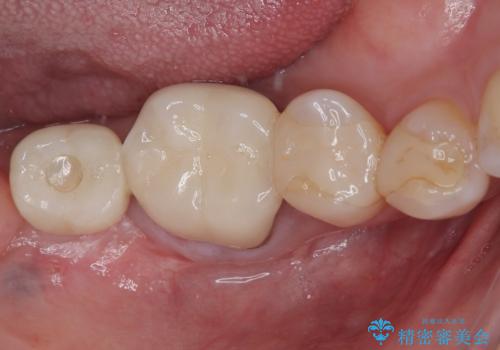

部分矯正を行ったこと治療期間は長くなりましたが、違和感のない咬み合わせを達成することができました。

放置した奥歯 部分矯正を併用したインプラント補綴治療